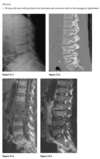

Anteroposterior view of the pelvis

shows diffuse,

uniform, bony sclerosis and a subtrochanteric frac-

ture of the proximal left femur.

A lateral chest ra-

diograph shows the

sandwich appearance of the vertebral bodies caused

by increased sclerosis of the superior and inferior

end plates.

Radiographs of the knees show splaying of the metaphyses and alternating radiolucent bands in the distal

femurs and proximal tibias and fibulas bilaterally. (Erlenmyer flask)

Diagnosis: Osteopetrosis

Defect in osteoclastic resorption.

Precocious (AR Lethal) and Delayed (AD asymptomatic)

Generalized osteosclerosis and diffuse cortical thick-

ening with narrowing of the medullary cavity.